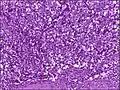

Histologia

O carcinoma de células escamosas surge da multiplicação descontrolada de células do epitélio e podem conter queratina e redes de filamentos ou desmossomos. Existem 6 sub-tipos: Adenoide, basaloide, células claras, células espinosas, células em anel de sinete e pleomórfico.

Pleomórfico, pobremente diferenciado, sem queratina.

Pleomórfico, pobremente diferenciado, sem queratina.